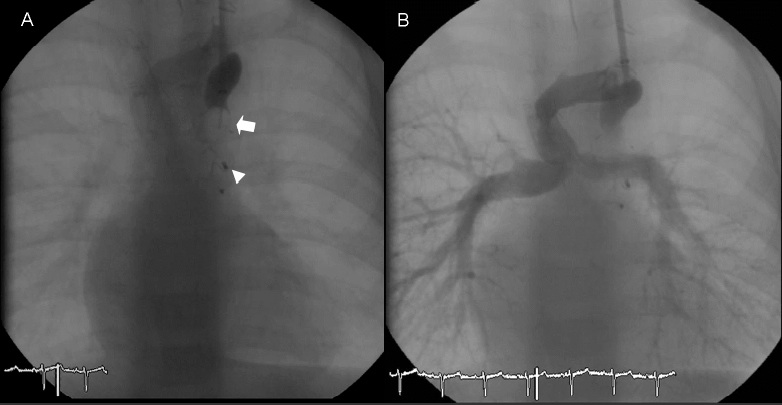

Under general anaesthesia, right heart catheterization was performed using a left internal jugular vein approach. Heparin was administered following our institutional protocol (100 IU per kilogram). A 6 French (Fr) sheath was inserted and a 5 Fr Berman catheter was used for hemodynamic assessment. Angiography showed a tortuous vessel (maximum diameter 6 mm) arising from the innominate vein and draining into the right atrium, corresponding with a left-sided superior vena cava (SVC) with high probability (Figure 1). A multipurpose catheter (MP1 4 Fr) was used to selectively cannulate the vessel and a 0.035 inch exchange wire was then positioned far into it. Over the wire, a 5 Fr guiding catheter was placed and an 8 mm Amplatzer vascular occluder (AGA Medical Corp., Plymouth, Minnesota) was deployed into the narrowest point of the vein (Figure 2A). Before releasing it, control angiography (Figure 2B) showed a significant residual shunt, and it was decided to use a larger device. A new 6 Fr guiding catheter was positioned into the vessel, and a 10 mm device was placed. An angiography performed 5 minutes later showed significant residual patency of blood flow. Thus, a 5 Fr Berman angiography catheter was positioned proximal to the plug and inflated for 10 minutes in order to interrupt the flow in the collateral vein (Figures 3A and 4). A new angiogram confirmed the absence of blood flow (Figure 3B). Subsequent control angiograms excluded the presence of other relevant collateral vessels. A significant rise in arterial blood saturation was noted (from 83% to 97%) immediately after the procedure.